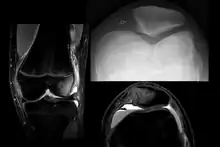

On X-ray, with skyline projections, dislocations are readily diagnosed. In borderline cases of subluxation, the following measurements can be helpful:

- The lateral patellofemoral angle, formed by:[16]

- A line connecting the most anterior points of the medial and lateral facets of the trochlea.

- A tangent to the lateral facet of the patella.

- With the knee in 20° flexed, this angle should normally open laterally.[16]

- The patellofemoral index is the ratio between the thickness of the medial joint space and the lateral joint space (L). With the knee 20° flexed, it should measure 1.6 or less.[16]